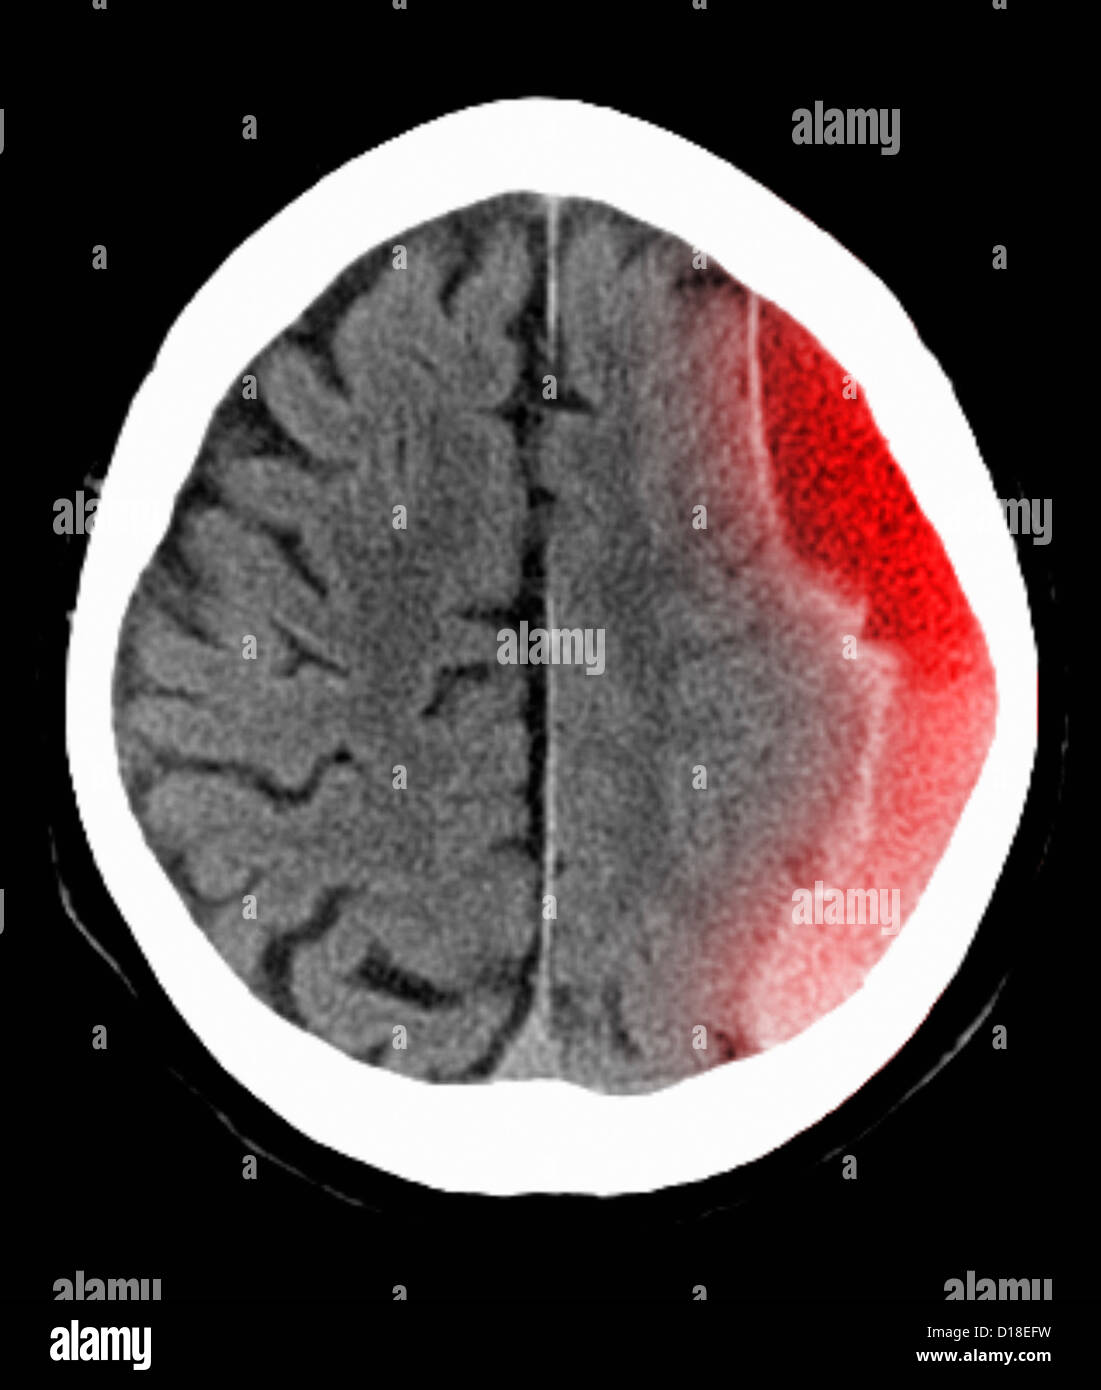

CT scan de la tête avec hématome sous Banque D'Imageshttps://www.alamyimages.fr/image-license-details/?v=1https://www.alamyimages.fr/photo-image-ct-scan-de-la-tete-avec-hematome-sous-52432797.html

CT scan de la tête avec hématome sous Banque D'Imageshttps://www.alamyimages.fr/image-license-details/?v=1https://www.alamyimages.fr/photo-image-ct-scan-de-la-tete-avec-hematome-sous-52432797.htmlRFD18EFW–CT scan de la tête avec hématome sous